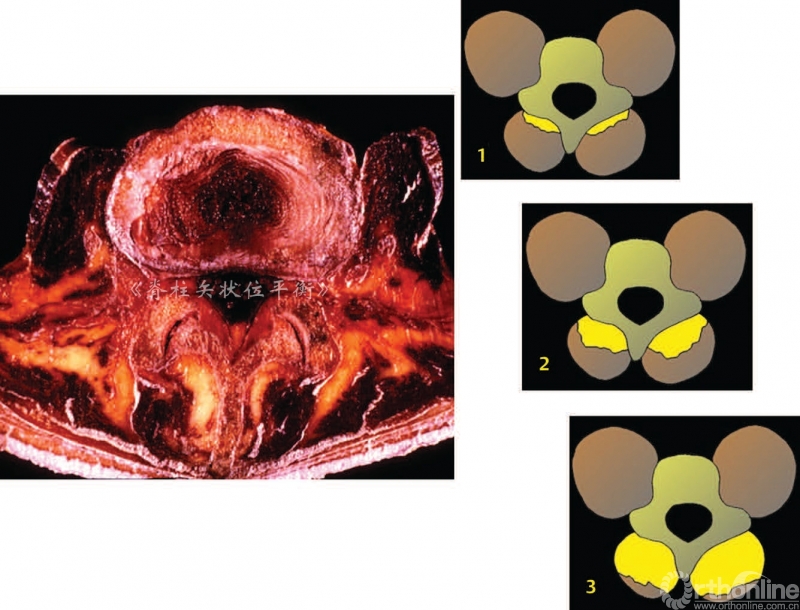

椎旁肌的退变以1型和2型肌肉纤维数量减少为特征。也可以观察到肌肉纤维,尤其是2型快速收缩纤维的萎缩。椎旁肌退变或者脂肪化过程是一种肌肉自然退变的现象,Hadar等[2]对腰骶部的肌肉进行量化,提出了脊柱后方肌群脂肪变性的三个时期。

● Ⅰ期:受累肌肉横断面脂肪变面积<50%

● Ⅱ期:脂肪变面积达 50%

● Ⅲ期:脂肪变面积>50%(图4)

图4 肌肉脂肪退变的 Hadar分期

肌肉脂肪化是从深部向表面发展,多裂肌是第一个受累的肌肉,从远端向近端进展(从腰骶部到胸腰部)。Cruz等[3]认为老龄化、腰椎前凸角度丢失和椎旁肌脂肪化程度三者之间呈正相关。